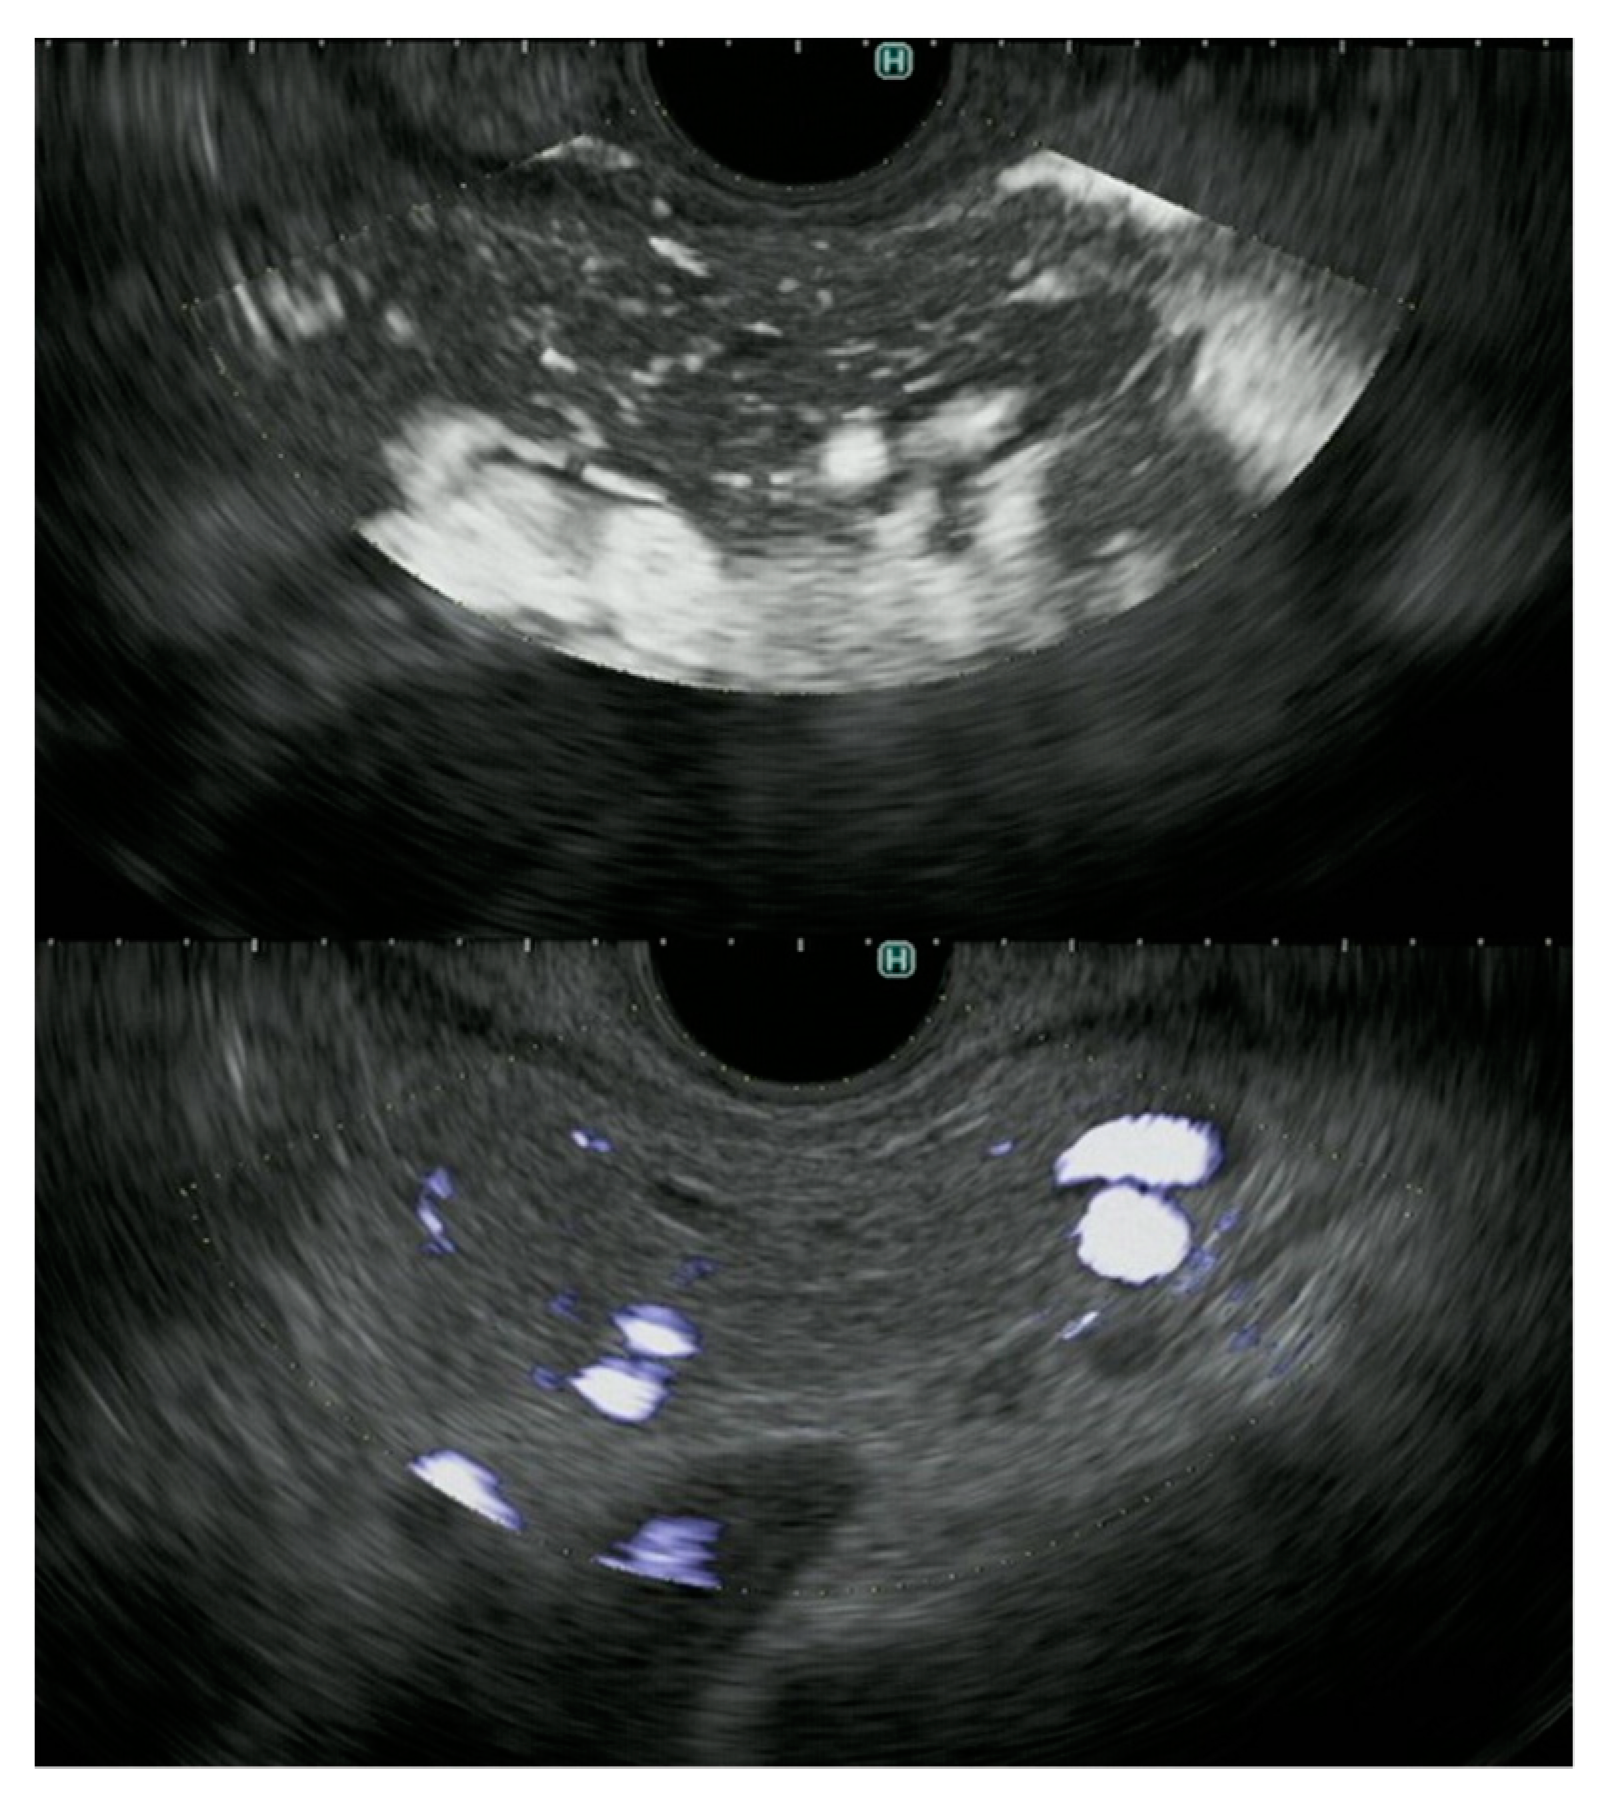

- Yamashita, Y.; Yoshikawa, T.; Kawaji, Y.; Tamura, T.; Hatamaru, K.; Itonaga, M.; Ida, Y.; Maekita, T.; Iguchi, M.; Murata, S.I.; et al. Novel endoscopic ultrasonography imaging technique for visualizing microcirculation without contrast enhancement in subepithelial lesions: Prospective study. Dig. Endosc. 2020, 33. [Google Scholar] [CrossRef]